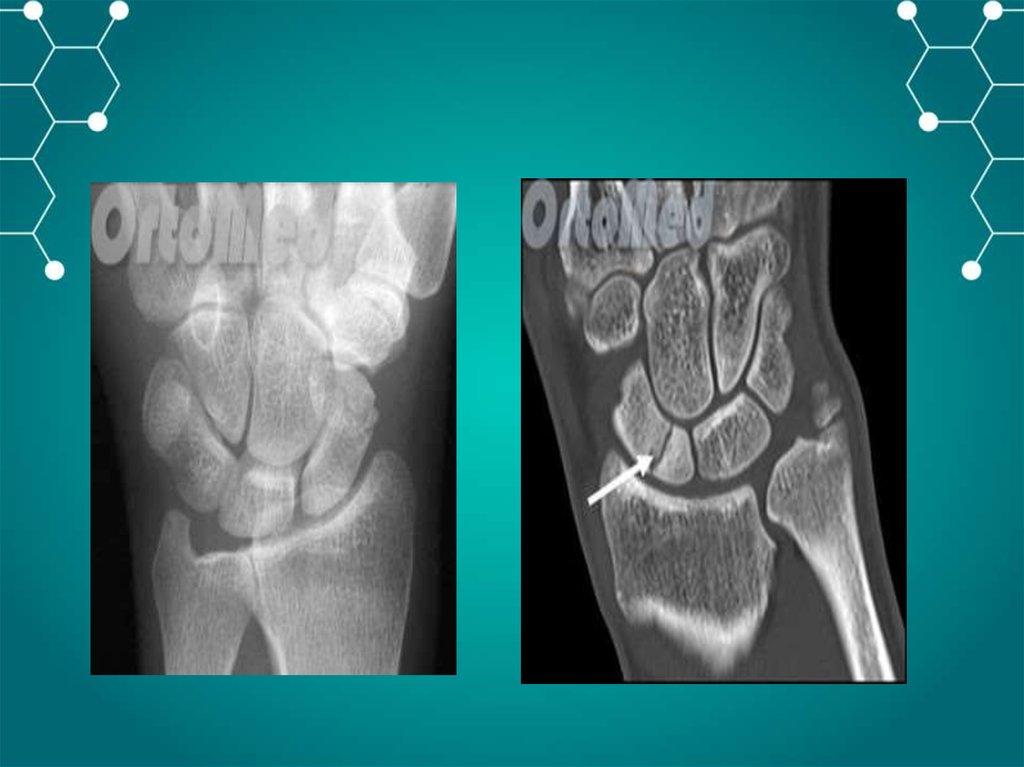

Частые перелом кисти